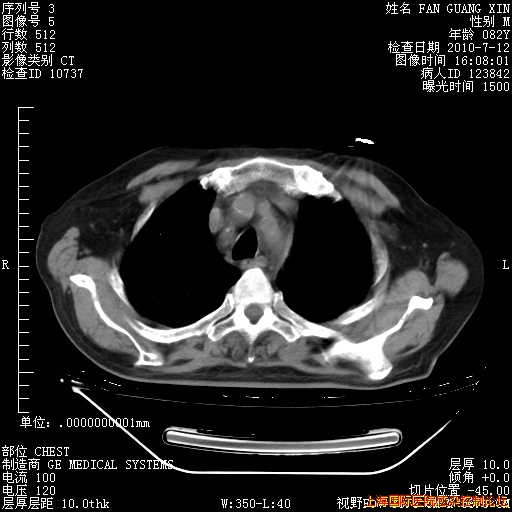

补发6月12日肺部CT肺窗

6月12日肺窗